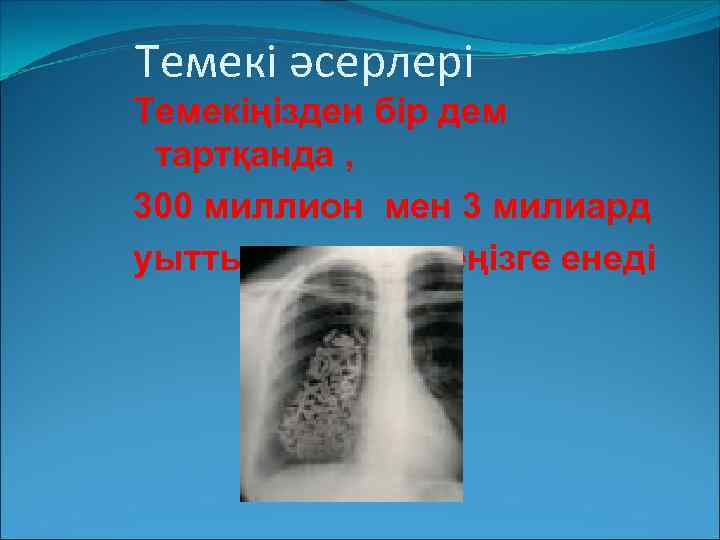

Темекі әсерлері Темекіңізден бір дем тартқанда , 300 миллион мен 3 милиард уытты заттар өкпеңізге енеді